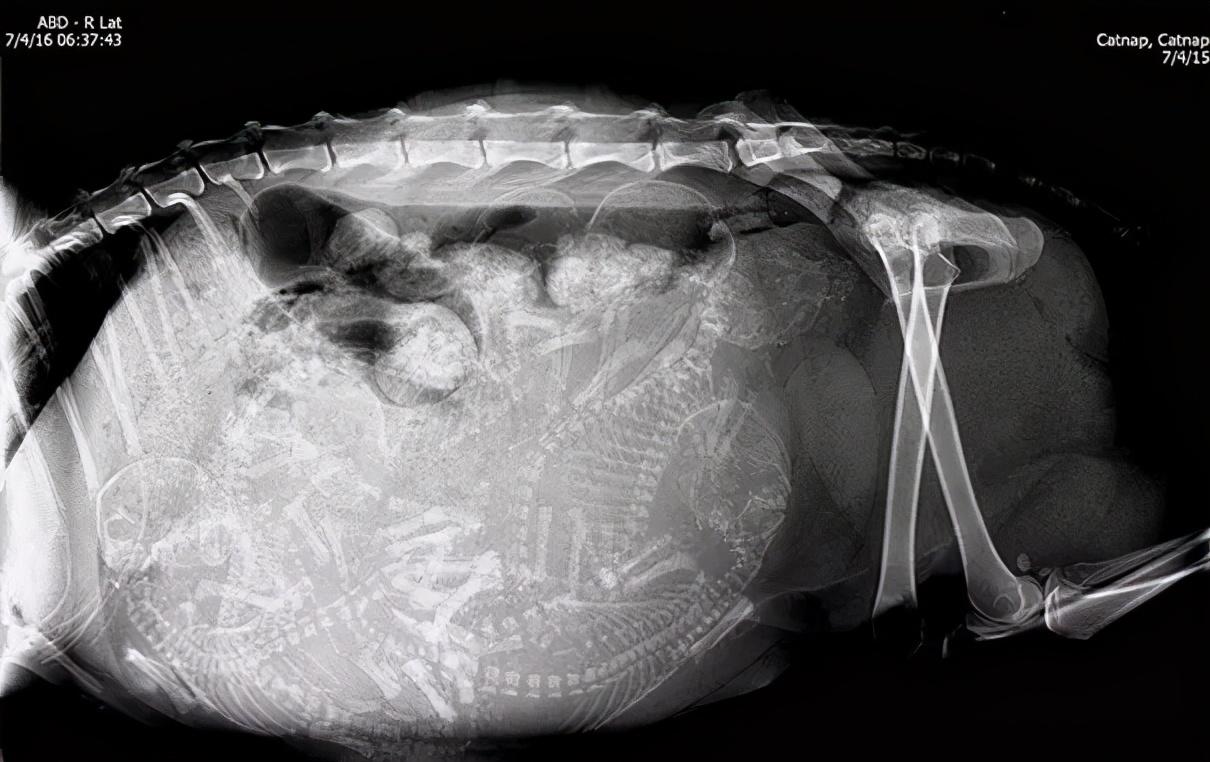

在大约46天后,才可以进行X光检查,来确定怀的小猫数量。